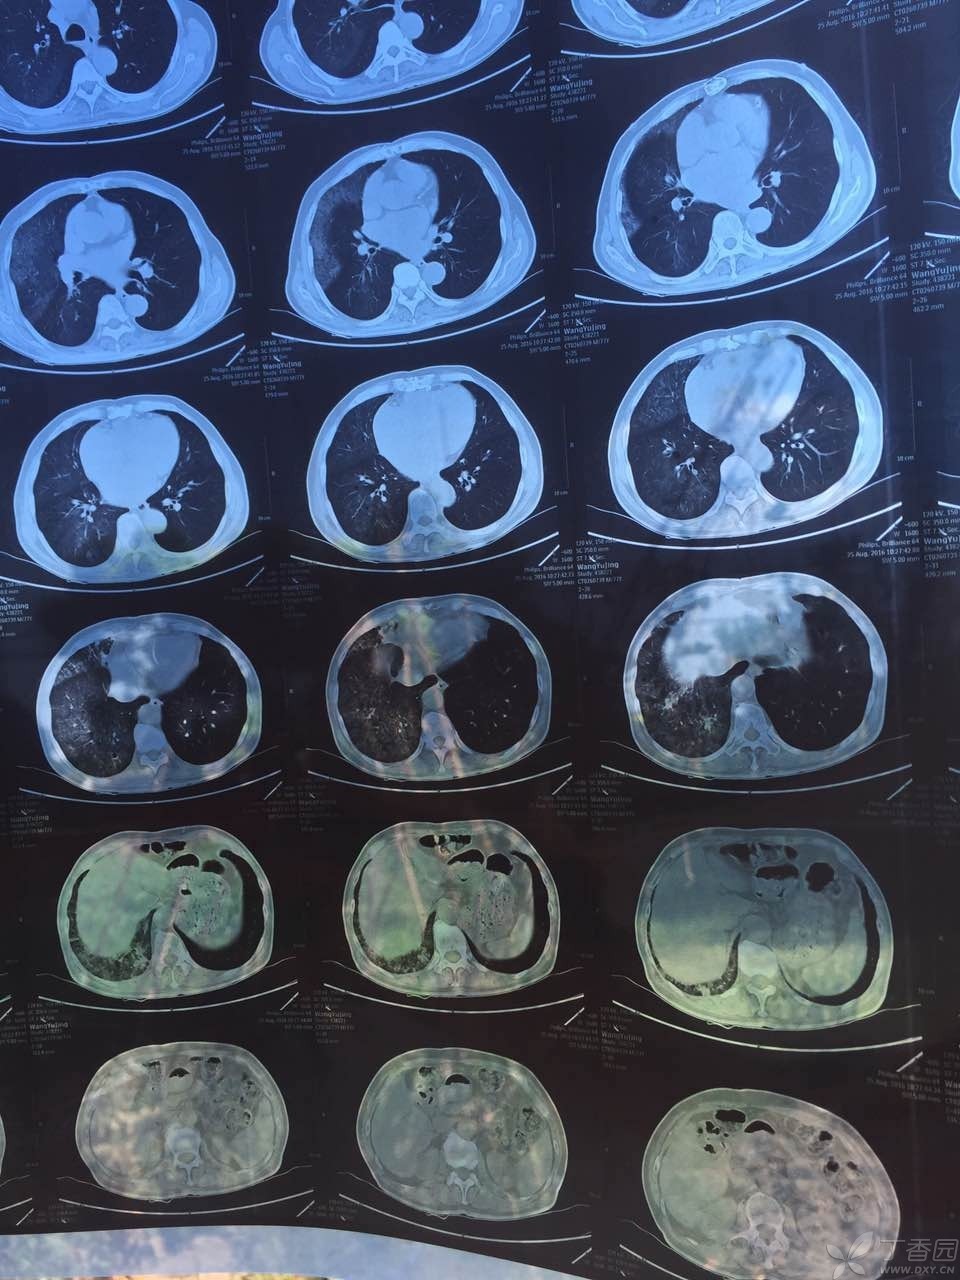

肺蛋白沉积症是一种罕见的疾病,它会导致异常蛋白质在肺部沉积,影响呼吸功能。作为一名医生,我亲眼目睹了许多患者因此疾病而受到困扰。在这篇文章中,我将探讨肺蛋白沉积症带来的挑战以及我们应对这些挑战的方法。

肺蛋白沉积症的早期症状往往不明显,容易被忽视。然而,及早发现并进行诊断和治疗是至关重要的。我们需要通过临床检查、影像学和组织活检等手段来确定诊断,并针对患者制定个体化的治疗方案。药物治疗、支持性护理和康复训练都是有效的治疗手段。